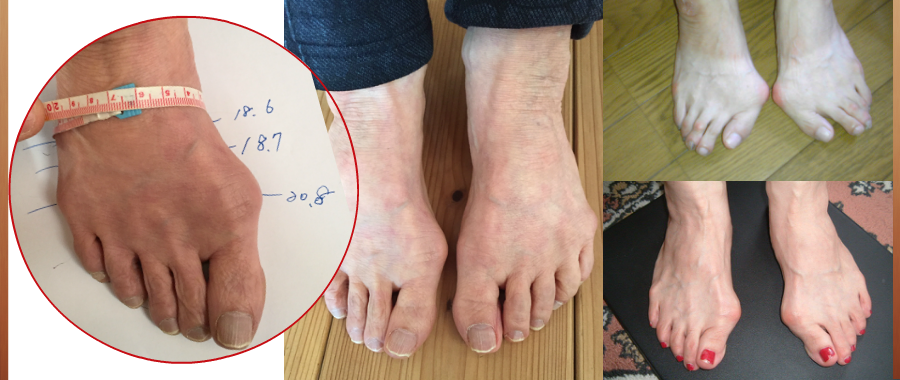

足に不適切な環境が痛みや外反母趾、内反小趾、ハンマートゥなど様々な症状に。

市販の靴でこのような変形、症状は作られますが、私どもの靴づくりは変形した足、痛みなどに対応し、靴型から作られます。

外反母趾、リウマチ、膠原病、など靴が足に合わない事で足の変形だけでなく、